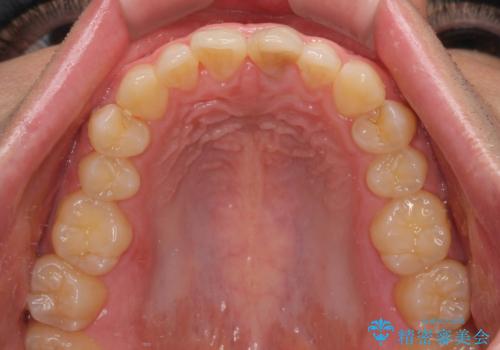

変色した前歯をオールセラミッククラウンに

- 転んだ際に欠けてしまった前歯の変色が気になるとのことで来院された患者様です。

診察やレントゲン写真より神経組織の失活が認められたため、根管治療、ファイバーコアによる土台築製後、オールセラミッククラウンにて補綴することとしました。

神経を取り除いた歯は時間とともに変色してきます。

クリーニングやホワイトニングでは改善できないため、オールセラミッククラウンなどによる補綴治療が必要となります。